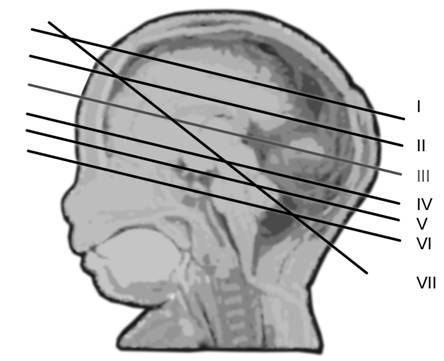

Fig. nr. 148 Planurile de sectiune transversala ecografica ale craniului fetal, demonstrate pe model anatomic (adaptat dupa Merz[8] )

Planul I - cel mai inalt plan axial. Cortexul cerebral hipoecogen localizat intre linia de mijloc si craniu.

Fig. nr. 149 Planul I de sectiune transversala.

Planul

II demonstreaza ventriculii laterali hipoecogeni si parte din plexurile

choroide ecogene.

Fig. nr. 150. Planul II de sectiune transversala a craniului fetal.

Planul III sau planul frontooccipital, pentru masurarea diametrelor biparietal si frontoocipital. Ecoul de mijloc frontoocipital este intrerupt in zona cavum septum pellucidi, anecogena, situata anterior de ventriculul III. Acesta este situat intre doi nuclei talamici hipoecogeni si apare ca o despicatura mica sau o linie.

Fig. nr. 151 Planul III de sectiune transversala a craniului fetal.

IV pune in evidenta ecoul liniei de mijloc, partial vizibil si mezencefalul

superior.

Fig. nr. 152. Planul IV de sectiune transversala

Planul V - trece prin partea bazala a mezencefalului si emisferele cerebrale. Pedunculii cerebrali formeaza aspectul de fluture, intre acestia apare fosa interpedunculara.

Fig. nr. 153. Planul V de sectiune transversala

Planul VI trece prin baza craniului si defineste fosele anterioara, mijlocie si posterioara. Osul sfenoidal hiperecogen apare la jonctiunea foselor anterioara cu posterioara. Portiunea joasa a cerebelului si puntea sunt vizibile.

Fig. nr. 154. Planul VI de sectiune frontala craniana.

Planul VII - plan oblic-transvers ce demonstreaza anterior cavum septum pellucidi si posterior cerebelul cu cisterna magna. In acest plan se poate evalua grosimea pliului nuchal intre 16 si 24 de saptamani (normal 5 mm) ce cuprinde tegument si tesut subcutanat, spre deosebire de translucenta normala din trim. I care este o acumulare de lichid.